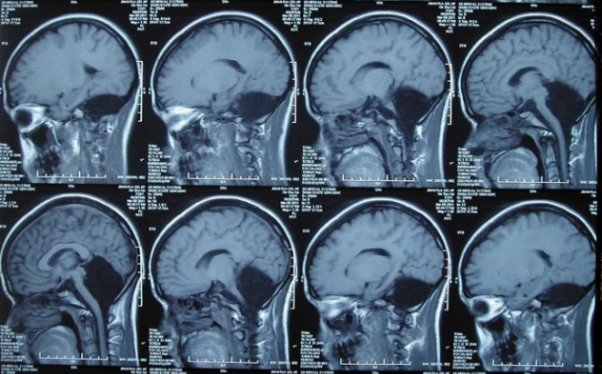

Slike možganov Kitajke brez možganov

Fotografija iz odprtih virov